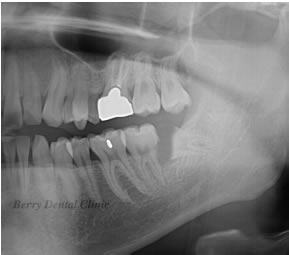

親知らずの抜歯 治療例

親知らずの抜歯も消炎処置をしても治癒しない場合は処置を行います。

左の実際のお口の中の画像ように親知らずが横になっている為プラークがたまりやすく親知らずの前の歯も虫歯になっています。

舌の2枚の画像はそのレントゲン画像で、左側はピンク色の歯ぐきを入れて加工しています。

右の画像のように歯ぐき画像のピンク色の部分を除去すると矢印の部分の親知らずの前の歯に黒い画像があり、それが虫歯になっている事を示します。

そのまま放置しているかぎり虫歯の歯の治療ができなので、抜歯になります。